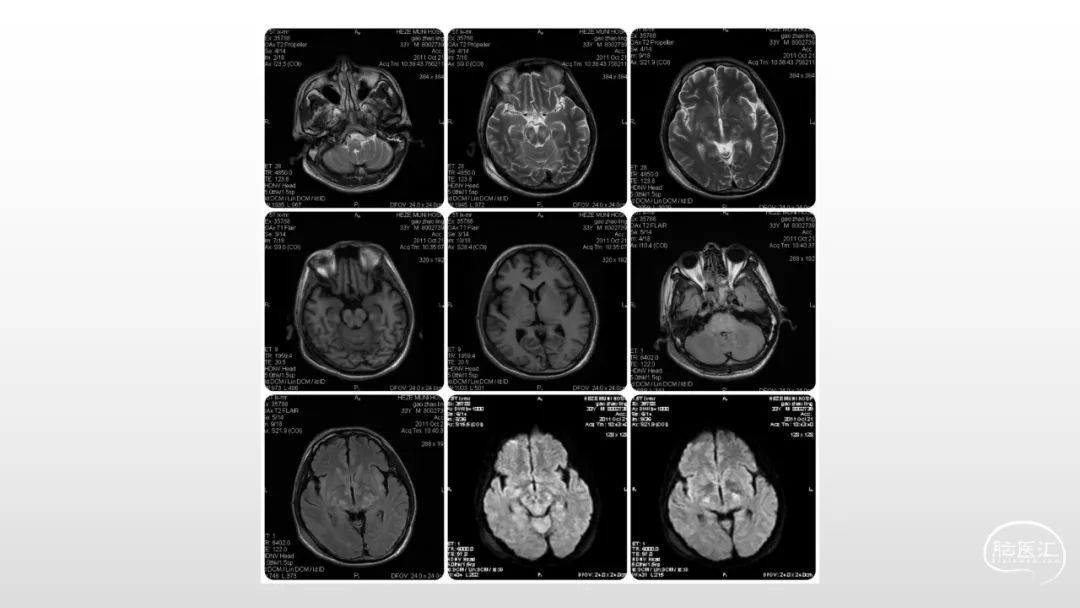

颅脑影像诊断基础知识讲座:感染和免疫性疾病1

马洪舟

菏泽市立医院